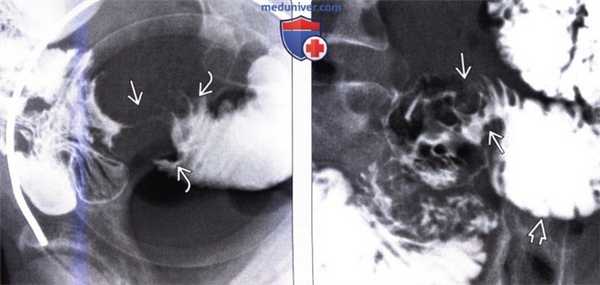

(а) На прицельной рентгенограмме при пассаже бария по тонкой кишке выявляется неравномерное утолщение складок кишки (стрелки).

(б) При КТ с контрастированием в коронарной проекции визуализируется сегментарное циркулярное утолщение стенки (стрелки) вовлеченного сегмента тонкой кишки с гомогенным накоплением контрастного вещества.

2. Рентгенография при раке тонкой кишки:

• Рентгеноскопия (энтероклизма):

о Инфильтративный тип опухоли характеризуется возникновением поражений по типу «огрызка яблока» или циркулярных:

- Четко отграниченное, циркулярное сужение просвета на коротком участке

- Неравномерное сужение просвета, подрытые края, возможно наличие язвы

- Узкая ригидная стриктура с престенотической дилатацией - Полиповидная опухоль на широком основании: растет в виде небольшой бляшки

о Полипоидная аденокарцинома на ножке (встречается редко)

(Слева) На рентгенограмме, полученной во время исследования пассажа бариевой взвеси по тонкой кишке, определяется стриктура терминальных отделов подвздошной кишки в виде «огрызка яблока» с сужением просвета, деструкцией слизистой оболочки и подрытыми краями. Эти изменения являются классическими признаками первичного рака тонкой кишки.

(Справа) На рентгенограмме, выполненной во время исследования пассажа контраста по тонкой кишке, визуализируется объемное образование В тощей кишки с наличием характерных признаков первичного рака тонкой кишки: узловидно утолщенных складок, деструкции слизистой оболочки и сужения просвета. Определяется дилатация отделов кишечника, расположенных выше уровня опухоли.